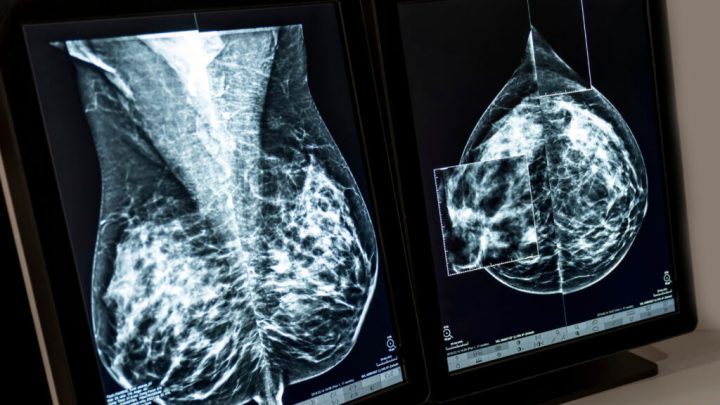

To speed adoption of breast cancer AI, a radiology network plots an acquisition April 17, 2025 By admin National radiology network Radnet to acquire iCAD for over $100 million for its breast cancer screening AI algorithm.